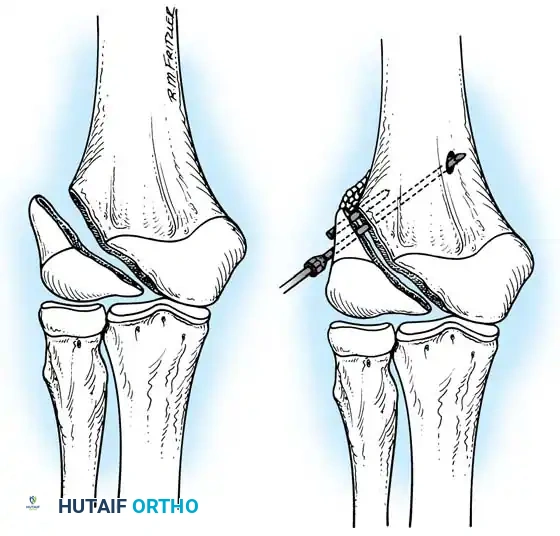

Percutaneous Leverage (Bernstein Technique)

Pesudo et al. and Bernstein et al. popularized the use of a percutaneous pin to manipulate the fracture fragments under fluoroscopy.

Anatomical Pitfall: During percutaneous reduction, the Kirschner wire must be introduced on the ulnar side of the radius. Introducing the wire laterally risks iatrogenic injury to the deep branch of the radial nerve (posterior interosseous nerve) as it traverses the arcade of Frohse.

Fig. 33-43 Radial neck fracture in relation to arcade of Frohse.

The Metaizeau Technique (Elastic Stable Intramedullary Nailing)

Gonzalez-Herranz et al. and Metaizeau revolutionized the treatment of displaced radial neck fractures (O’Brien types II and III) using retrograde intramedullary pinning. This technique boasts excellent results in over 94% of cases.

- Entry Point: A small incision is made over the distal lateral radial metaphysis, taking care to protect the superficial radial nerve.

- Pin Preparation: A steel Kirschner wire or titanium elastic nail (TEN) is sharply bent at the distal 1.5 cm.

- Insertion: The wire is advanced retrograde through the medullary canal until the bent tip engages the displaced proximal epiphysis.

- Reduction: The pin is rotated 180 degrees around its long axis. The bent tip acts as a cam, elevating the radial head and shifting it medially into anatomical position beneath the lateral condyle.

Fig. 33-44 A-D, Reduction of radial head by leverage method and retrograde intramedullary pinning with Kirschner wire.